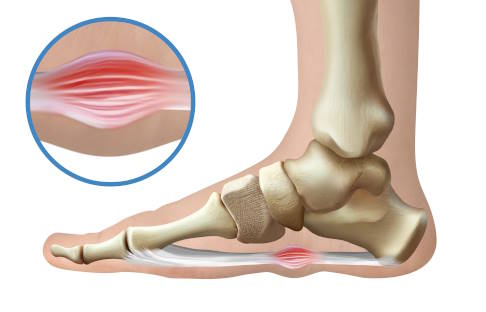

Bei Morbus Ledderhose bilden sich die bindegewebigen Knoten und Stränge an der Plantarfaszie. Das ist die auch als Plantaraponeurose bezeichnete 3 bis 4 mm dicke Sehnenplatte der Fußsohle, die vom Fersenbein fächerförmig zu den Zehen verläuft. Am häufigsten sitzen die Knoten im Bereich des Zehenstrahls der Großzehe und der beiden danebenliegenden Zehen, also eher an der Innenseite der Fußsohle. Die Erkrankung ist chronisch, wobei sich die knotigen Veränderungen und Verhärtungen meist schubförmig über Monate bis Jahre hinweg ausbilden. In seltenen Fällen können die Verdickungen auch akut entstehen. Das ist z. B. bei einem Riss der Plantarfaszie mit anschließender Vernarbung denkbar.

Typischerweise berichten die Patienten selbst von den entdeckten Knoten an der Fußsohle und den dadurch verursachten Beschwerden. Mittels Inspektion und Abtasten kann der Arzt dann die umschriebenen Veränderungen an der Fußsohle und am Fußinnenrand leicht erkennen. Im Ultraschall lassen sich die Veränderungen gut darstellen und bestätigen.